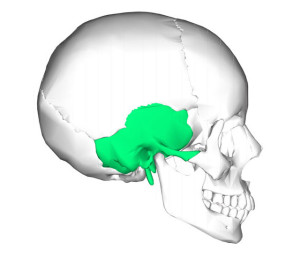

Височная кость является очень сложной костью человеческого организма. Ее строение состоит из многочисленных элементов: борозд, поверхностей, каналов, бугорков и прочего. Расположена височная кость на границе между основанием и сводом черепа. С иными элементами черепной коробки височная кость соединена различными видами соединений.

Можно выделить следующие основные части строения кости:

- барабанная часть,

- чешуя височной кости,

- каменистая часть или пирамида.

Парная сложная височная кость выполняет следующие важные функции организма:

- содержит в себе органы гравитации и слуха,

- образует часть боковой стенки и основания черепа,

- через каналы этой кости проходят сосуды и нервы.

Височная кость — парная кость, расположенная по бокам и у основания черепа, латеральнее височной доли коры головного мозга. Височные кости прилегают к боковым частям головы, называемым висками, где соединяются четыре черепные кости. Каждый висок покрыт височной мышцей.